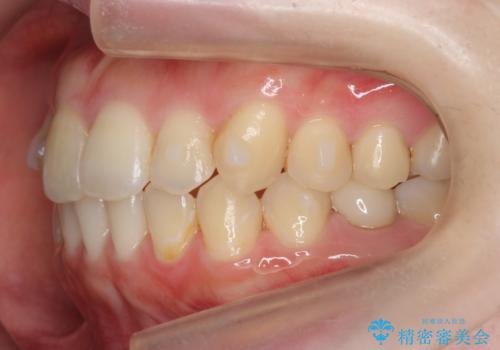

犬歯のねじれ 上の歯が引っ込んでいる

- 前歯の並びを気にして来院。

インビザラインで、上の前歯をやすり掛けして並べました。

途中妊娠、出産を挟み、患者様がアライナーがつけられない時期もあって治療自体は延長しました。